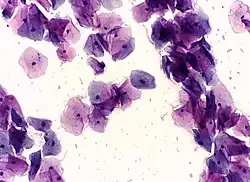

Endocervical adenocarcinoma on a pap test. -